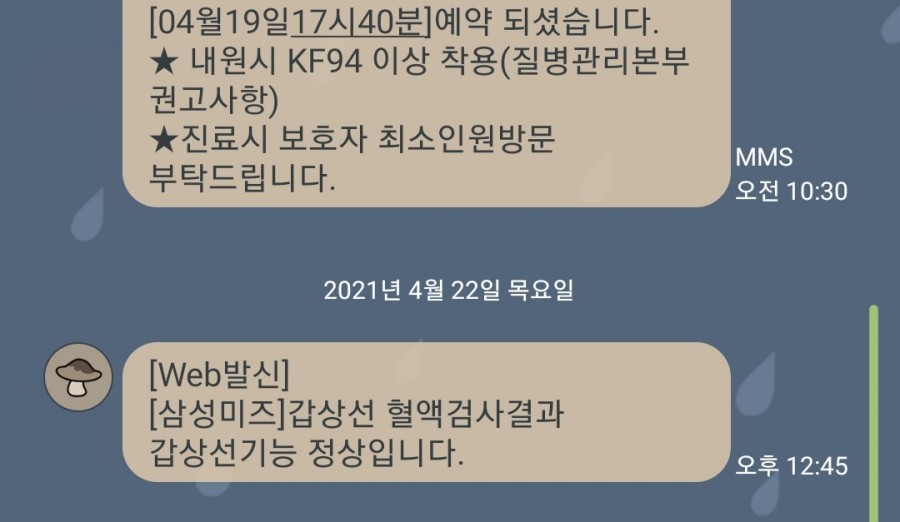

원래 갑상샘 기능 저하증이 있었기 때문에 갑상샘병원과 산부인과를 2주일마다 다니느라 바쁘다.

첫 번째 검사는 갑상선 기능 저하가 의심되는 소견으로 재검사가 이루어졌으며 두 번째 갑상선 혈액검사 결과 정상으로 나왔다. 휴대약을 꾸준히 먹고 있는 상태라 정상적으로 나오지만 간혹 수치가 떨어지기 때문에 여전히 주기적인 검사를 하고 있다.

3주 후에 다시 병원을 방문하기로 했다.